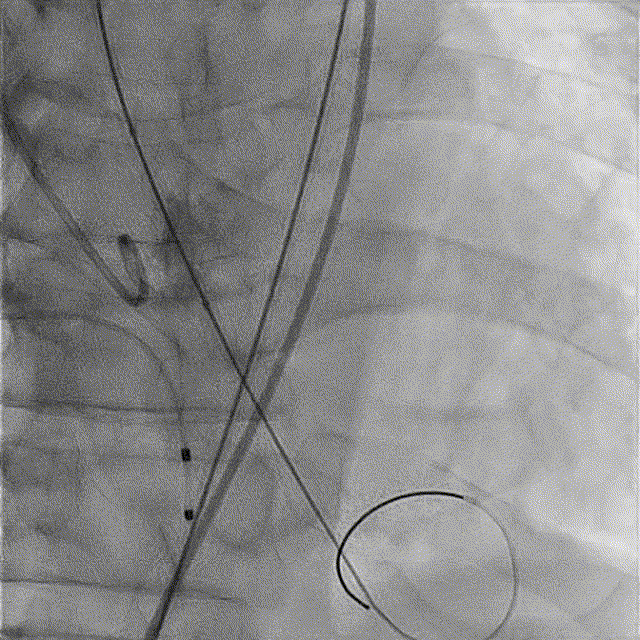

TaurusNXT植入过程

全麻后超声引导下建立入路,左侧股动脉置入TaurusNavi 20F血管鞘。跨瓣后左室放置Lunderquist导丝,使用TaurusAtlas 20mm球囊预扩,球囊无明显位移,有轻微腰征、无漏。输送系统预备同侧Snare从右股动脉送入,安全顺利通过主动脉弓。瓣膜在双窦展开位约瓣上2mm位初始定位释放,工作位造影多角度评估后予以释放(一次定位释放,未采用多次回收功能)。超声下显示瓣膜偏椭圆,之后使用TaurusAtlas 22mm球囊后扩,支架形态改善明显,导管测压由术前的70mmHg即刻下降至1mmHg,术后即刻超声心动图评估显示瓣膜位置良好,微量瓣周漏,血流动力学指标理想。

术中影像

主动脉根部造影

球囊预扩

预备Snare跨瓣

瓣膜初始定位

工作位造影(双窦展开位)

完全释放

球囊后扩

最终造影